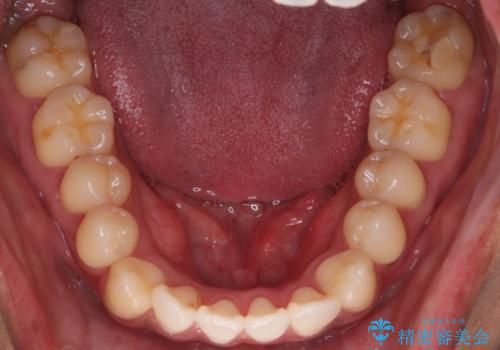

【審美装置】開口(オープンバイト)を改善

- 全体的に歯並びをよくしたいとのことで来院されました。初診時、患者様はセラミック矯正とワイヤー矯正で迷われていました。

開口(オープンバイト)のため噛み合わせを考慮してワイヤー矯正を提案させていただきました。

IPR(歯と歯の間を削る処置)と顎間ゴムを行い歯並びを整える治療計画を立てました。